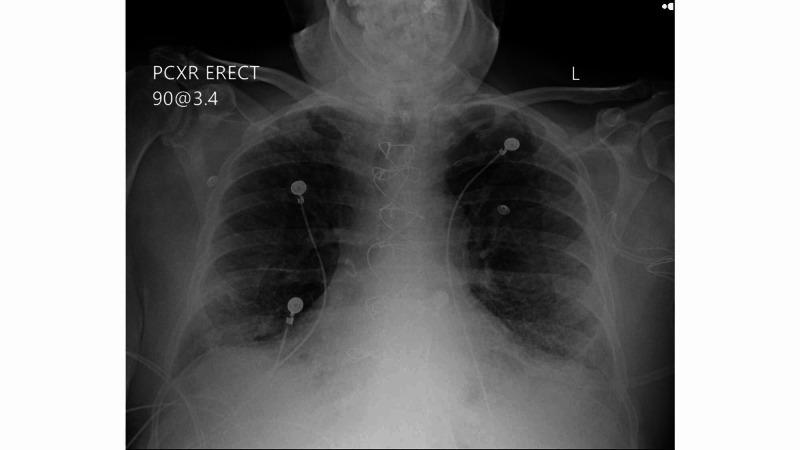

Background Pneumonia caused by severe acute respiratory syndrome coronavirus 2 (SARS-CoV-2) can cause severe inflammation of the lungs resulting in acute respiratory distress syndrome (ARDS). Current treatment guidelines support use of remdesivir as well as dexamethasone in hypoxic patients. There is very little information known about use of inhaled corticosteroids (ICS) in combination with the other two medications. Methods and outcomes We report our experience among six coronavirus disease 2019 (COVID-19) patients who received ICS, remdesivir and dexamethasone for treatment as well as their outcomes. Data were obtained from retrospective chart review during a two-week period from July 8, 2020 to July 22, 2020. Five patients were treated successfully and discharged home. One patient expired. Conclusions This case series highlights the possible benefits of inhaled steroids in treatment of COVID-19 patients with hypoxia. Further randomized controlled studies are needed to assess inhaled corticosteroids as possible treatment either alone or in combination with systemic steroids for treating COVID-19 patients. Dose and optimal duration need to be studied and evaluated.